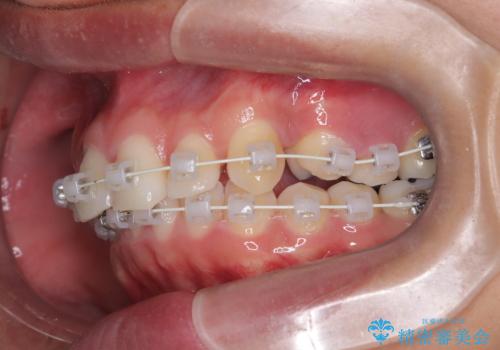

- 矯正装置

- ワイヤー(審美装置)

叢生(歯のデコボコ)の量が多く、加えてディープバイト(過蓋咬合)や重度の捻転も認められたため、リンガルアーチやマイクロインプラントなどの補助装置を併用し、治療を進めました。

治療途中では咬み合わせの改善を目的としてバイトアップを行い、歯の捻転や叢生を改善しつつ、機能的に安定した咬合を獲得しています。